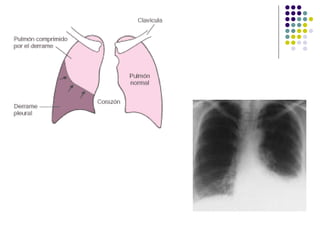

COMPLICACIONES QUIRURGICAS DERRAME PLEURAL:- Es el acúmulo anormal de un exceso de líquido en la cavidad torácica que resulta del desequilibrio entre la formación del líquido pleural y su remoción ETIOLOGIA:- 1.-Enfermedades de la pleura o los pulmones. 2.-Alteraciones extrapulmonares:- **Cardíacas (ICC),Renales (síndrome nefrótico), hepáticas  (cirrosis con ascitis), pancreáticas (pancreatitis). **Enfermedades sistémicas (LES, artritis reumatoidea), o  por reacción a drogas (nitrofurantoina). **Neoplásico.

COMPLICACIONES QUIRURGICAS MANIFESTACIONES CLINICAS:- 1.- Dolor pleurítico. 2.- Disnea. 3.- Taquipnea. 4.- Disminución del murmullo vesicular y  frémito vocal, de la expansibilidad  torácica, matidez. TRATAMIENTO:- 1.- Drenaje (Toracocentesis).

COMPLICACIONES QUIRURGICAS DERRAMEPLEURAL:- Es el acúmulo anormal de un exceso de líquido en la cavidad torácica que resulta del desequilibrio entre la formación del líquido pleural y su remoción ETIOLOGIA:- 1.-Enfermedades de la pleura o los pulmones. 2.-Alteraciones extrapulmonares:- **Cardíacas (ICC),Renales (síndrome nefrótico), hepáticas (cirrosis con ascitis), pancreáticas (pancreatitis). **Enfermedades sistémicas (LES, artritis reumatoidea), o por reacción a drogas (nitrofurantoina). **Neoplásico.

COMPLICACIONES QUIRURGICAS MANIFESTACIONESCLINICAS:- 1.- Dolor pleurítico. 2.- Disnea. 3.- Taquipnea. 4.- Disminución del murmullo vesicular y frémito vocal, de la expansibilidad torácica, matidez. TRATAMIENTO:- 1.- Drenaje (Toracocentesis).